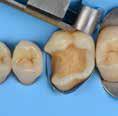

Why immediate dentine sealing?

Resin infiltration into the dentine surface is more effective on freshly cut dentine because it is uncontaminated and clean. Immedciate Dentine Sealing protects dentine against contamination with bacteria or remnants of temporary cements. It prevents post-operative sensitivity by sealing dentine tubules. It increases bond strength of the final indirect restoration to the tooth. It often eliminates the need for anaesthesia during the cementation procedure (when the restoration is delivered in the next appointment).

• Placing a rubber dam and isolating neighbouring teeth with teflon tape are always recommended.

• Use maximum air pressure to dry 1-PRIMER of G2-Bond to remove the solvent & residues of water.

• 1-PRIMER should be kept out of light as it contains photoinitiators.

• When doing immediate dentine sealing with G-Premio BOND, it is recommended to add a thin layer of G-aenial® Universal Injectable or a flowable composite on top.

1. Clean the tooth surfaces, rinse thoroughly and dry Apply G-Premio BOND Apply 1-PRIMER of G2-BOND Universal

5. Air dry to make a uniform bonding layer

4. Light cure

5. Fill in the undercuts with everX Flow®. Perform deep margin elevation if needed.

6. Remove unpolymerized layer. Expose enamel covered with adhesive with a fine grit diamond bur.

2A. G-Premio BOND

2B. G2-BOND Universal